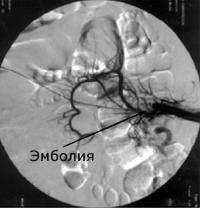

![Ангиография позволяет поставить точный диагноз и выполнить вмешательство по восстановлению кровообращения]()

Рентгеновская ангиография

Метода введения контрастного вещества непосредственно в интересующие артерии. Проводится через доступ к артериям на руке или на ноге. Позволяет прицельно изучить проходимость брыжеечных артерий и одновременно выполнить вмешательство по восстановлению проходимости закупоренной артерии. Ренгтеноангиография выступает диагностическим и лечебным методом одновременно. С помощью специальных катетеров и инструментов возможно проведение рассасывания тромбов (тромболизиса) или его удаления - тромбэктомии.